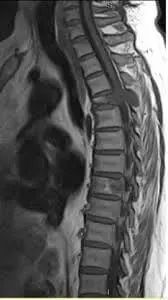

Найлегше було б почати з «модних» гриж дисків. Але наша багаторічна практика (а також світовий досвід) показують, що грижа диска в грудному відділі хребта – це велика рідкість. Нижче наведено МРТ грижі диска грудного відділу хребта – випадок вкрай рідкісний.

Якщо грижа грудного відділу хребта і виявляється на МРТ, то вона, як правило, не є основною причиною болю.